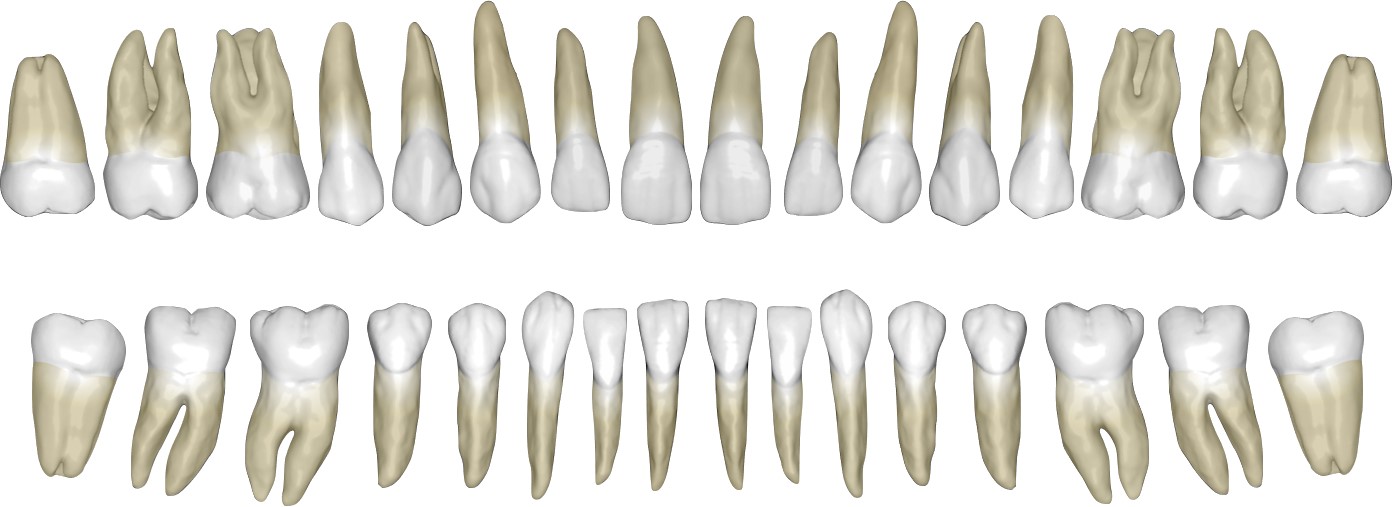

牙齿矢量图素材 | Keynote+PPT双平台可编辑 | 每颗牙独立图层 正畸教学必备

专业牙齿矢量图素材库,Keynote与PowerPoint双平台完美兼容!每颗牙齿独立图层设计,支持单独移动、缩放、改色,无需专业绘图软件,打开即用。包含完整牙列、单颗牙解剖图、咬合关系、正畸支抗示意图等20+模板,专为牙科教学、正畸方案演示、医学科普课件打造。

✅ 精细到每颗牙:32颗牙齿独立矢量图层,精准调整位置与形态

✅ 正畸场景全覆盖:托槽定位、支抗控制、牙齿移动路径等专业图示一键调用

✅ 高清矢量无损缩放:适配手机端展示、大屏投影、印刷物料多种场景